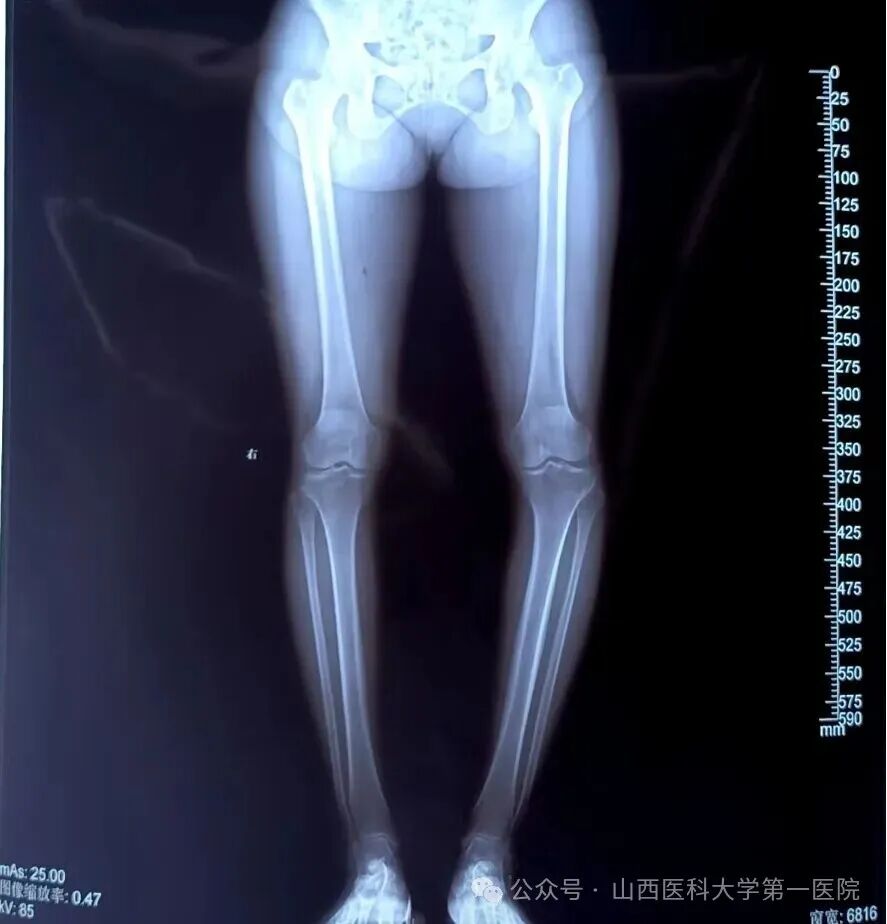

术后左下肢力线明显矫正